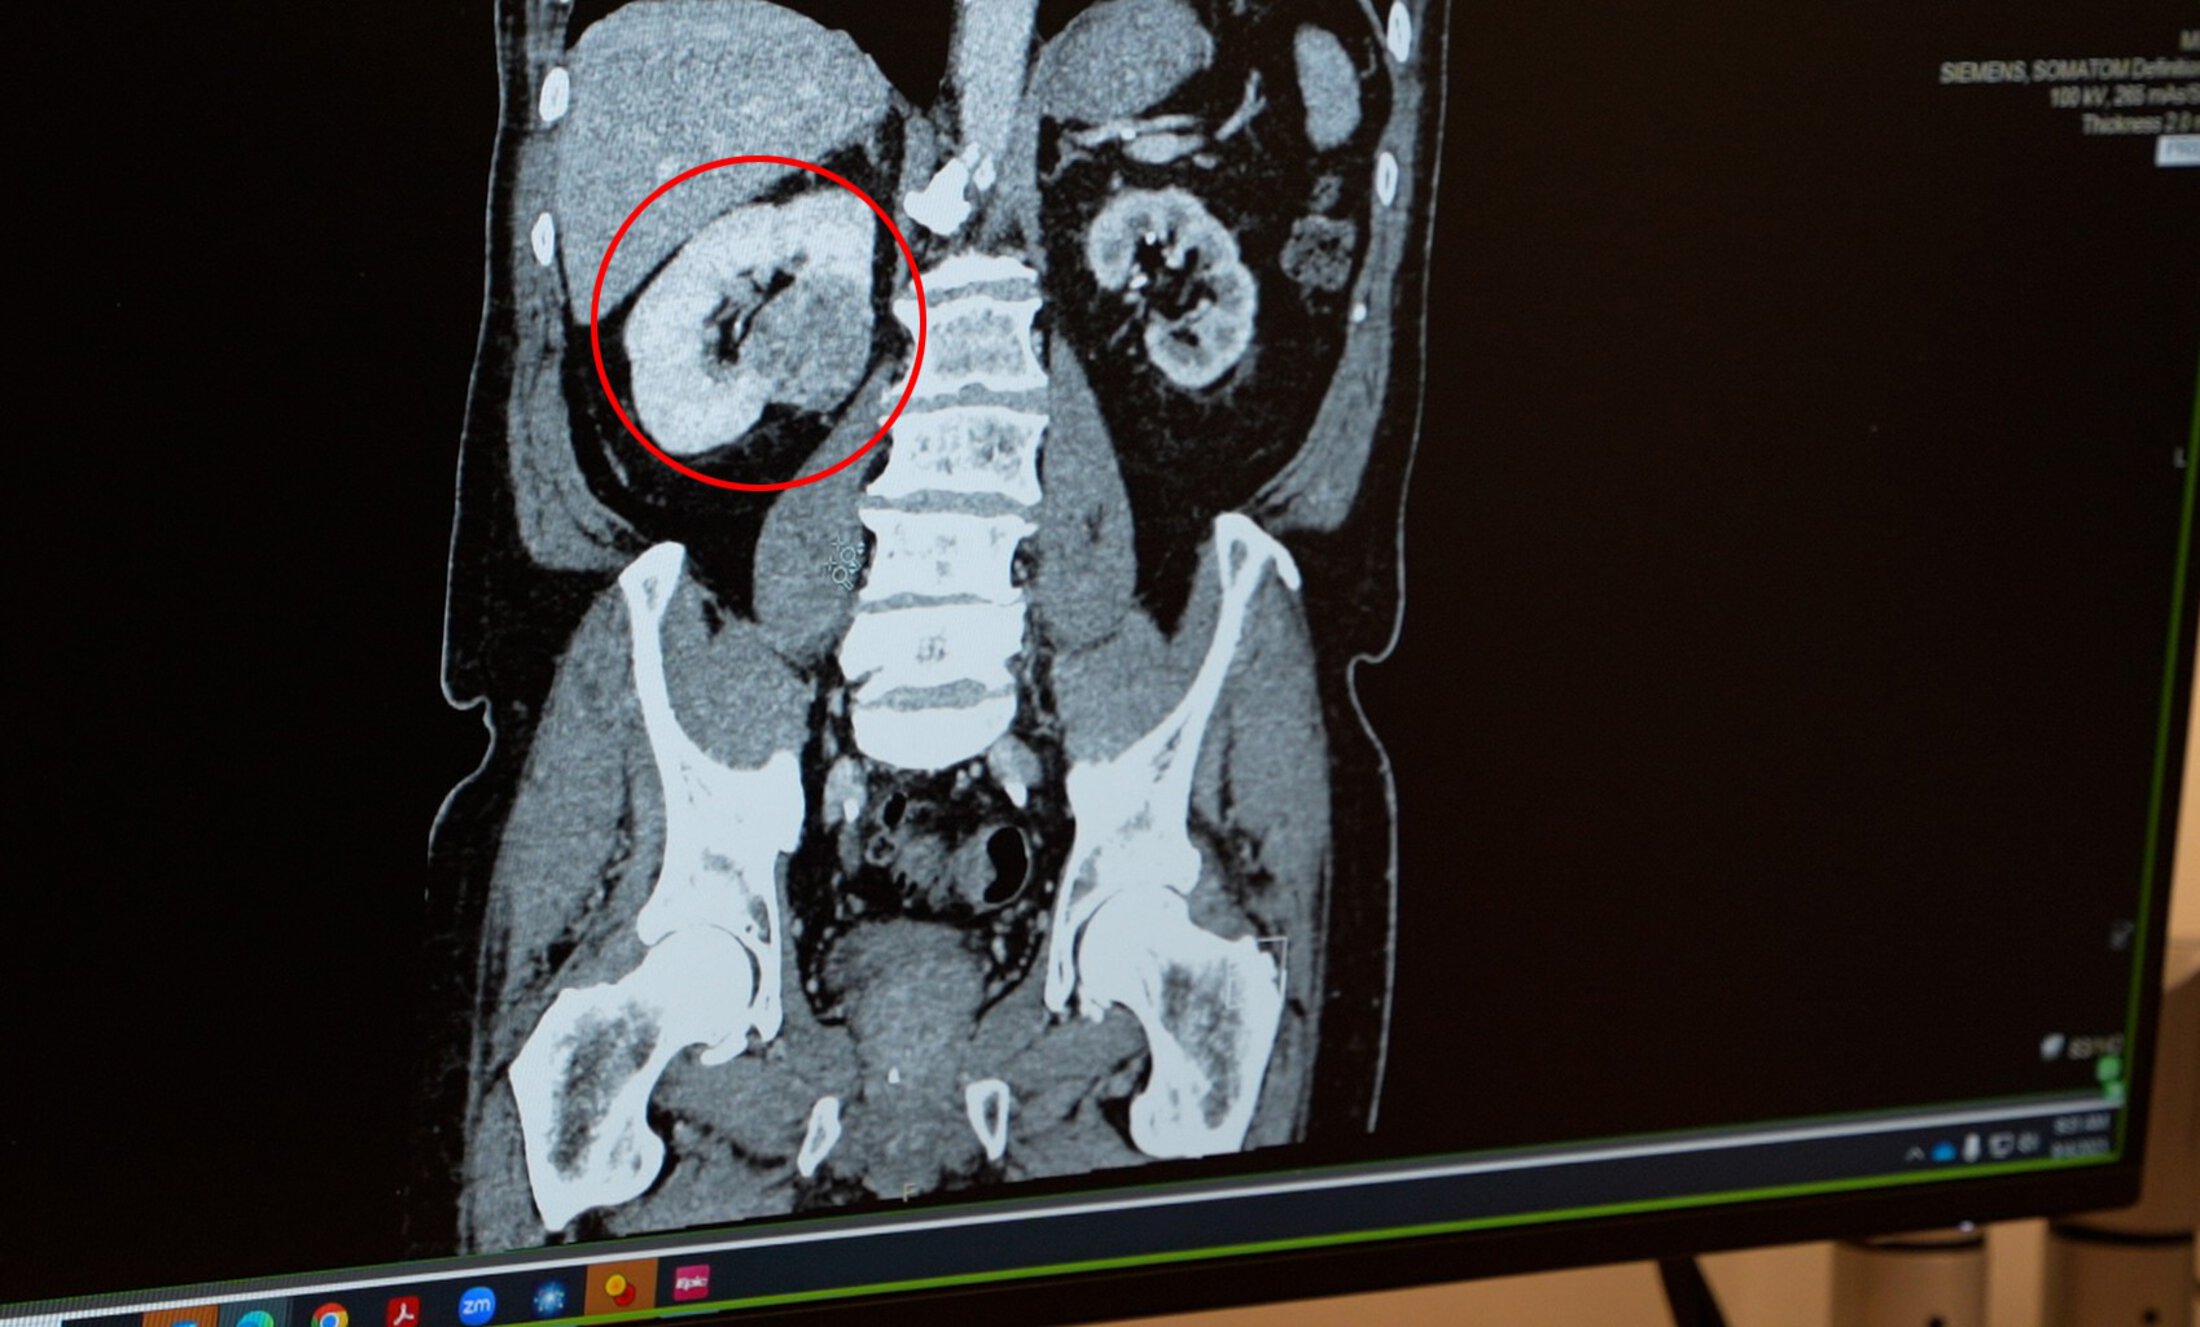

an abdominal scan

A scan reveals the tumor pressing against the spine.

In early 2024, an MRI revealed grim news: one kidney essentially nonfunctional, the other kidney damaged, and a cancerous tumor in between. The tumor was lodged in the damaged kidney and pushing on his spine. Surgery was not an option, as removing the tumor risked what little kidney function Smith had left.

“His case was challenging because the tumor was in the center of the kidney,” explained Brian Lally, M.D., Smith’s radiation oncologist at MUSC Hollings Cancer Center. “Making it even more complex is that our kidneys move as we breathe. I had to treat the tumor while accounting for that motion and making sure not to destroy the working kidney.”